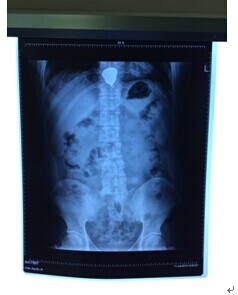

7月11日中午,消化科接到急诊科请求会诊电话,一名青年男子突发胸骨后疼痛伴胸闷气急症状急需会诊,许丰副主任闻讯后立即赶赴急诊科,经追问病史,患者因与家属“怄气”吞服了一枚金佛像,X片也提示金属异物嵌顿于食管。考虑到该异物随时会导致食管穿孔、感染和出血,危及患者生命,许主任决定必须立即对患者实施内镜下取异物术。经与患者家属沟通后,患者迅速被送到门诊六楼内镜中心。术中,许主任发现,患者食管下段嵌顿着一枚大小约3.5cm的金色异物,于是迅速采用异物钳将其取出。异物取出后一看,原来为一枚印有佛像的金制挂件,术后,患者难受症状立即缓解。